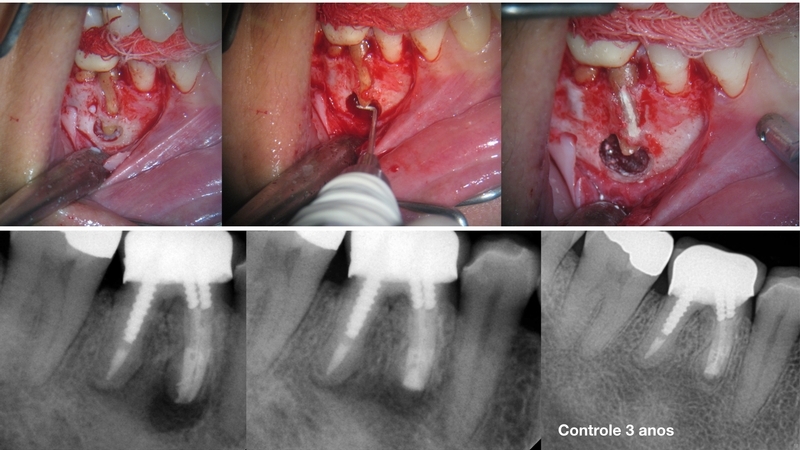

Muitas vezes a indicação cirúrgica é motivada por iatrogenias envolvendo a estrutura radicular. Desvios em terços médios não permitem a interferência na causa do processo patológico, ficando portanto o terço apical sem tratamento. Portanto para interferir no processo teria portanto, que ressectar a raiz no nível do desvio. Entretanto, o remanescente dentário ficaria com pouca estrutura. Então, para solucionar o problema, removendo a causa sem perder grande parte da estrutura, é feito uma canalização envolvendo o terço apical até o nível do desvio. Realizado com ultrassom e inserto diamantado, faz-se uma canaleta e preenche com MTA. Ficando a raiz com comprimento satisfatório.

A canalização só deve ser realizada nestas condições ou em casos de fissura radicular limitada, no terço médio de raízes de dentes apoio de pontes fixas, sem receber carga direta.